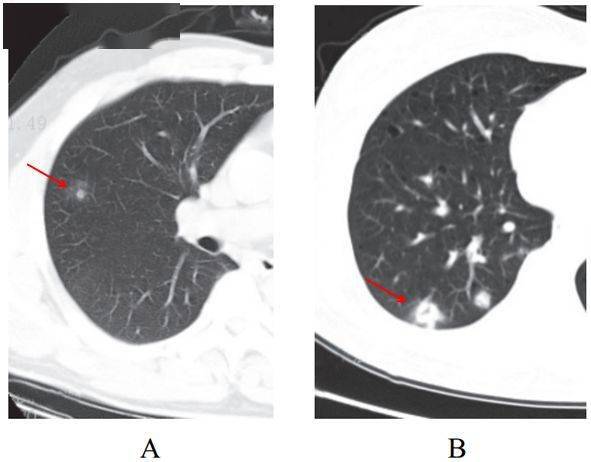

(五)结节伴晕征

部分案例 实性结节病灶周围出现磨玻璃密度影,边缘模糊,称为晕征

根据既往病理学机制提示,病灶中心实变影为肺泡腔内聚集大量富细胞渗出液,显示为实性密度灶;其周围肺泡亦见渗出,包含炎症细胞、蛋白质、纤维素等,形成“膜状物”,或形成磨玻璃密度阴影(图 2-5)

图 2-5结节伴晕征(A和B)